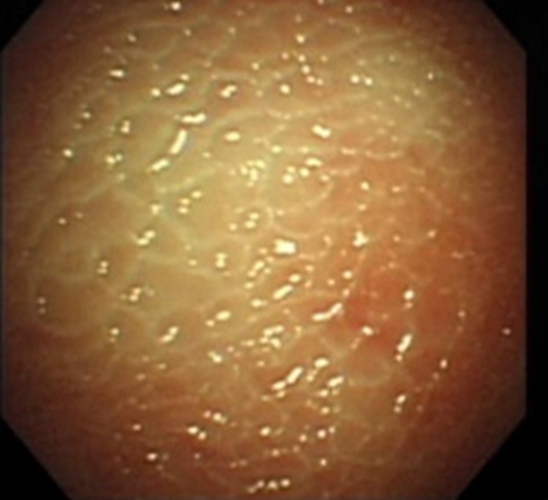

結核性胸膜炎胸腔的積液

結核性胸膜炎胸腔積液的

結核性胸膜炎胸腔積液